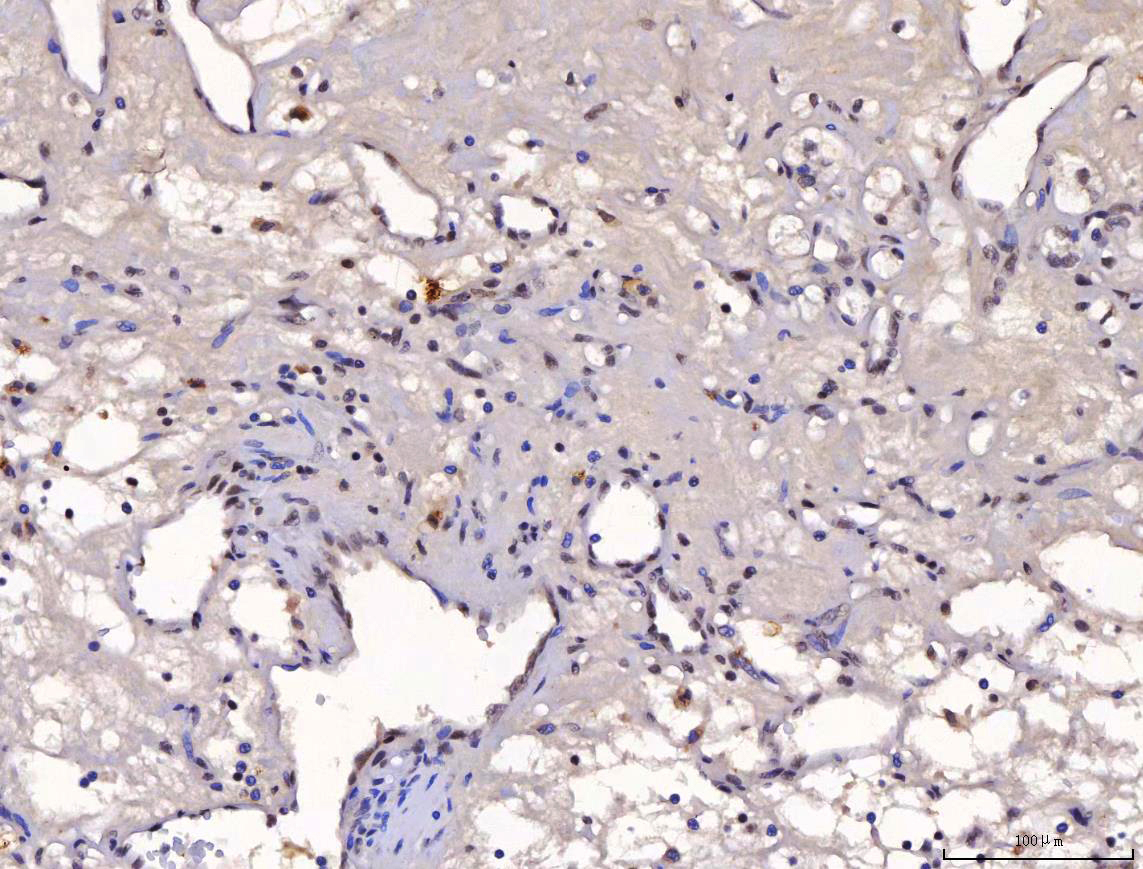

IHC analysis of YY1 using anti-YY1 antibody (M00833-2).

YY1 was detected in a paraffin-embedded section of human renal clear cell carcinoma tissue. The tissue section was incubated with mouse anti-YY1 Antibody (M00833-2) at a dilution of 1:200 and developed using HRP Conjugated mouse IgG Super Vision Assay Kit (Catalog # SV0001) with DAB (Catalog # AR1027) as the chromogen.